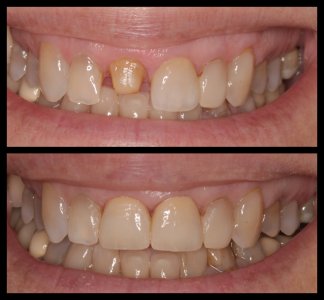

ΠΡΟΣΘΕΤΙΚΕΣ ΑΠΟΚΑΤΑΣΤΑΣΕΙΣ ΜΕ ΣΥΝΔΥΑΣΜΟ ΛΕΥΚΑΝΣΗΣ, ΣΥΝΘΕΤΩΝ ΡΗΤΙΝΩΝ ΚΑΙ ΟΛΟΚΕΡΑΜΙΚΩΝ ΟΨΕΩΝ ΚΑΙ ΣΤΕΦΑΝΩΝ

ΠΕΡΙΣΤΑΤΙΚΑ ΜΕ ΤΟΠΟΘΕΤΗΣΗ ΕΝΔΟΟΣΤΙΚΩΝ ΕΜΦΥΤΕΥΜΑΤΩΝ. ΌΠΟΥ ΧΡΕΙΑΣΤΗΚΕ ΠΡΑΓΜΑΤΟΠΟΙΗΘΗΚΕ ΑΝΑΠΛΑΣΗ ΟΣΤΟΥ ΚΑΙ ΟΥΛΙΚΩΝ ΕΛΕΙΜΜΑΤΩΝ ΜΕ ΧΡΗΣΗ ΜΟΣΧΕΥΜΑΤΩΝ ΚΑΙ PRF